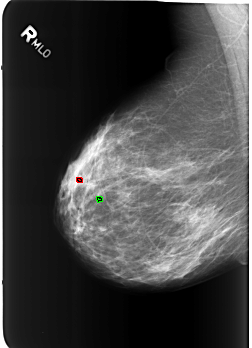

B_3213_1.RIGHT_MLO

FILE: B_3213_1.RIGHT_MLO.OVERLAY

TOTAL_ABNORMALITIES 2

ABNORMALITY 1

LESION_TYPE CALCIFICATION TYPE ROUND_AND_REGULAR-LUCENT_CENTER DISTRIBUTION N/A

ASSESSMENT 2

SUBTLETY 5

PATHOLOGY BENIGN_WITHOUT_CALLBACK

TOTAL_OUTLINES 1

BOUNDARY

ABNORMALITY 2